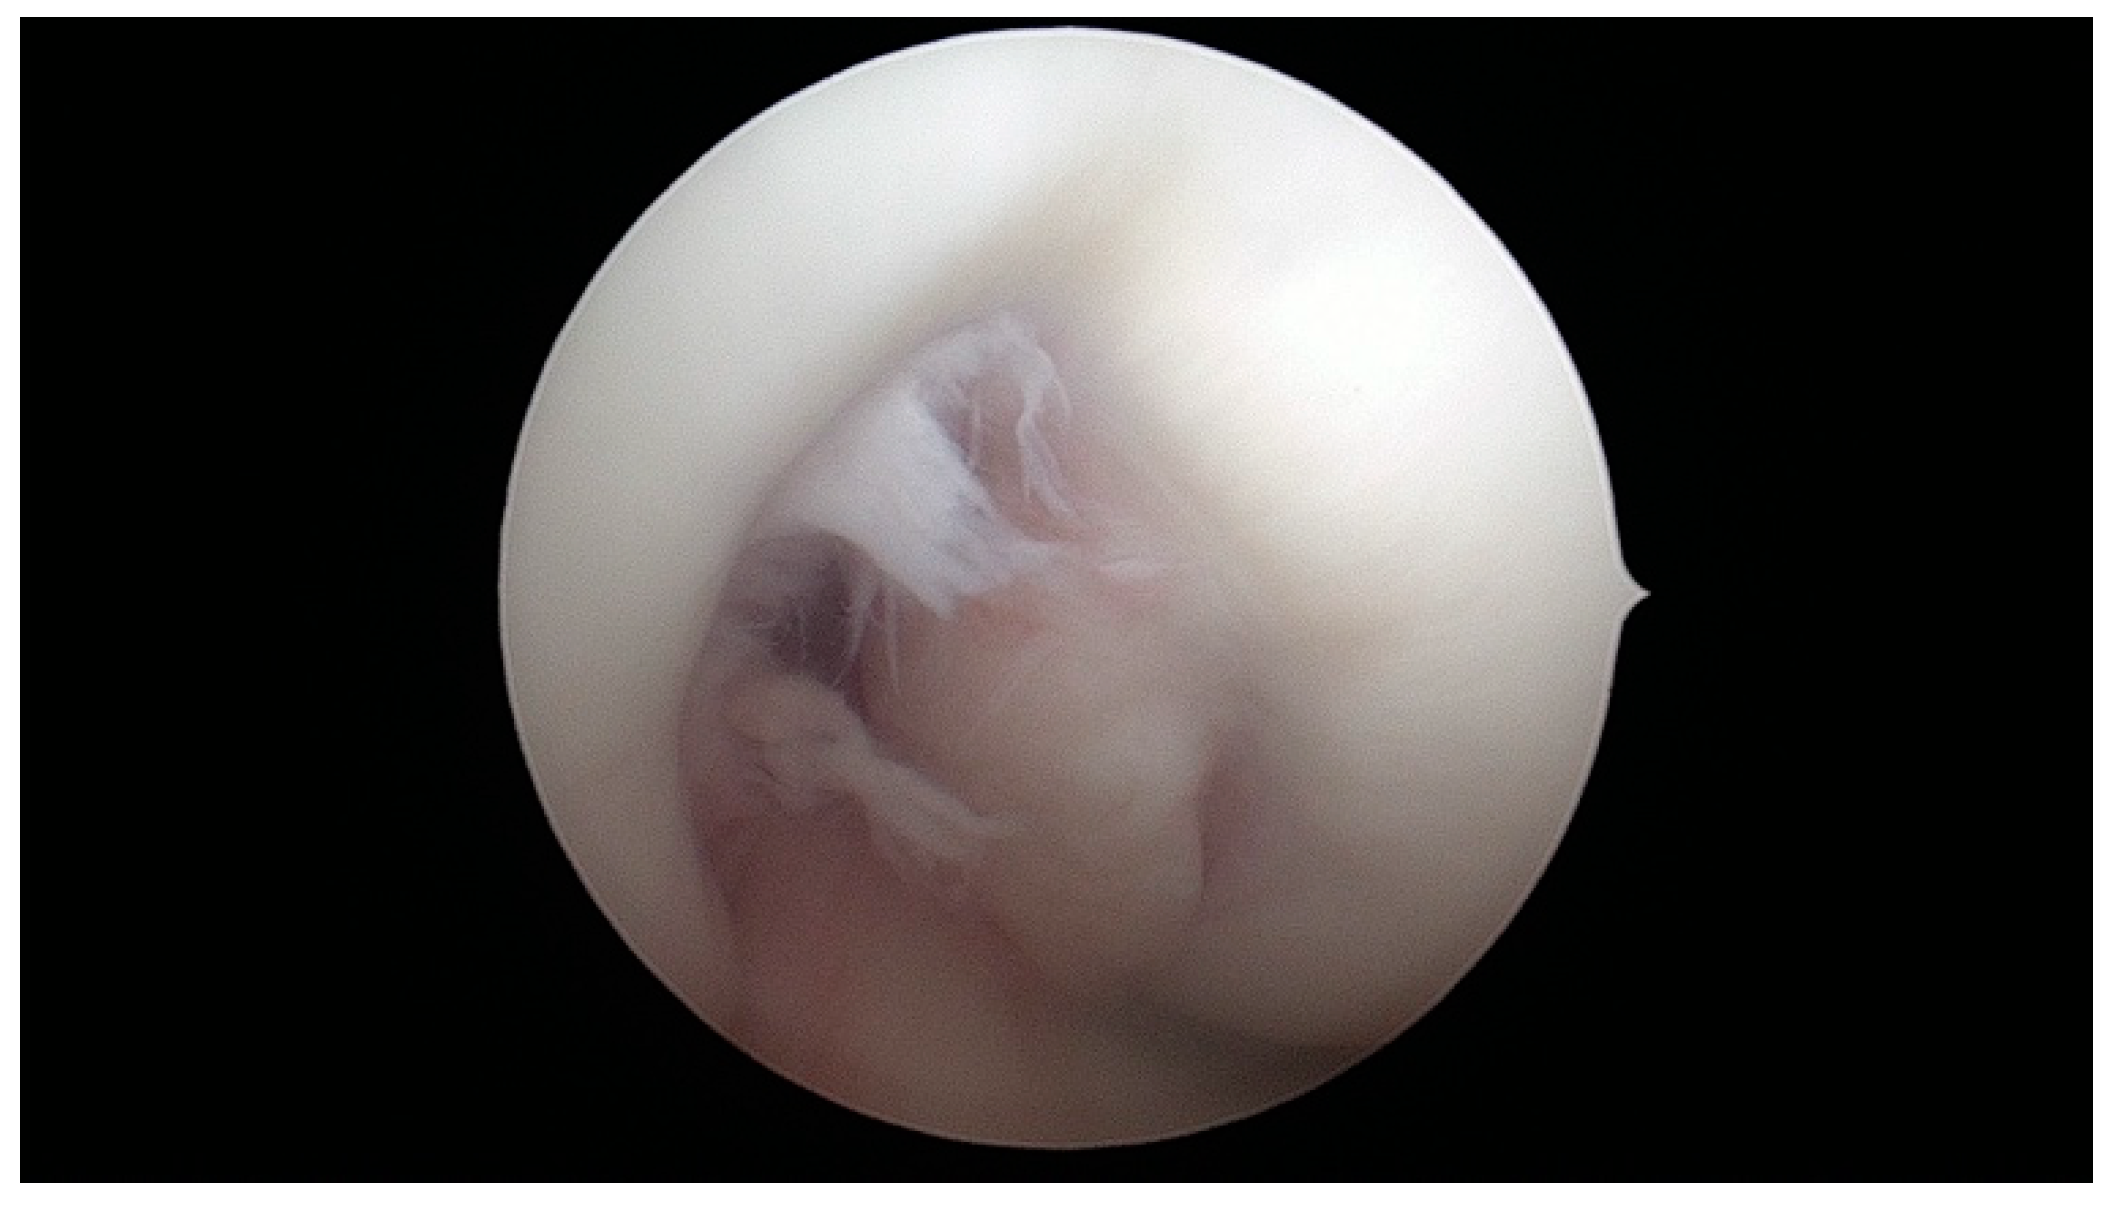

- aICN area: area of the circle defined by three cortical walls of the antero-superior notch (in the custom axial plane/CAP; Figure 3).

- ACL area: area of the closed polygon defined by pointed dots around the cross-section of the anterior cruciate ligament (in the CAP; Figure 4).

- aICN area and ACL area (both appear in Figure 6).